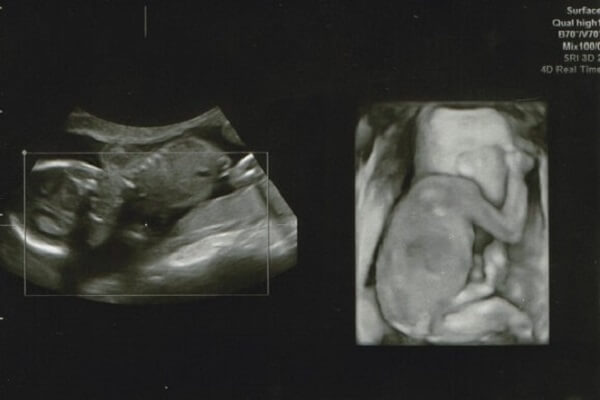

2Dエコー

一般的に妊婦検診で利用されているエコーです。2Dのエコーでは、赤ちゃんの身体の断面を映し出すため、平面的な写真を撮ることができます。

3Dエコー

3Dエコーはその名の通り、3次元(長さ・幅・奥行き)の超音波で、赤ちゃんの立体的な写真(静止画)を撮ることができます。

4Dエコー

4Dエコーとは、3Dに「時間」の概念を加え、4次元にしたもの。3Dエコーでは静止画しか見られないのに対し、赤ちゃんのしぐさや表情といった動きを動画で見ることができます。